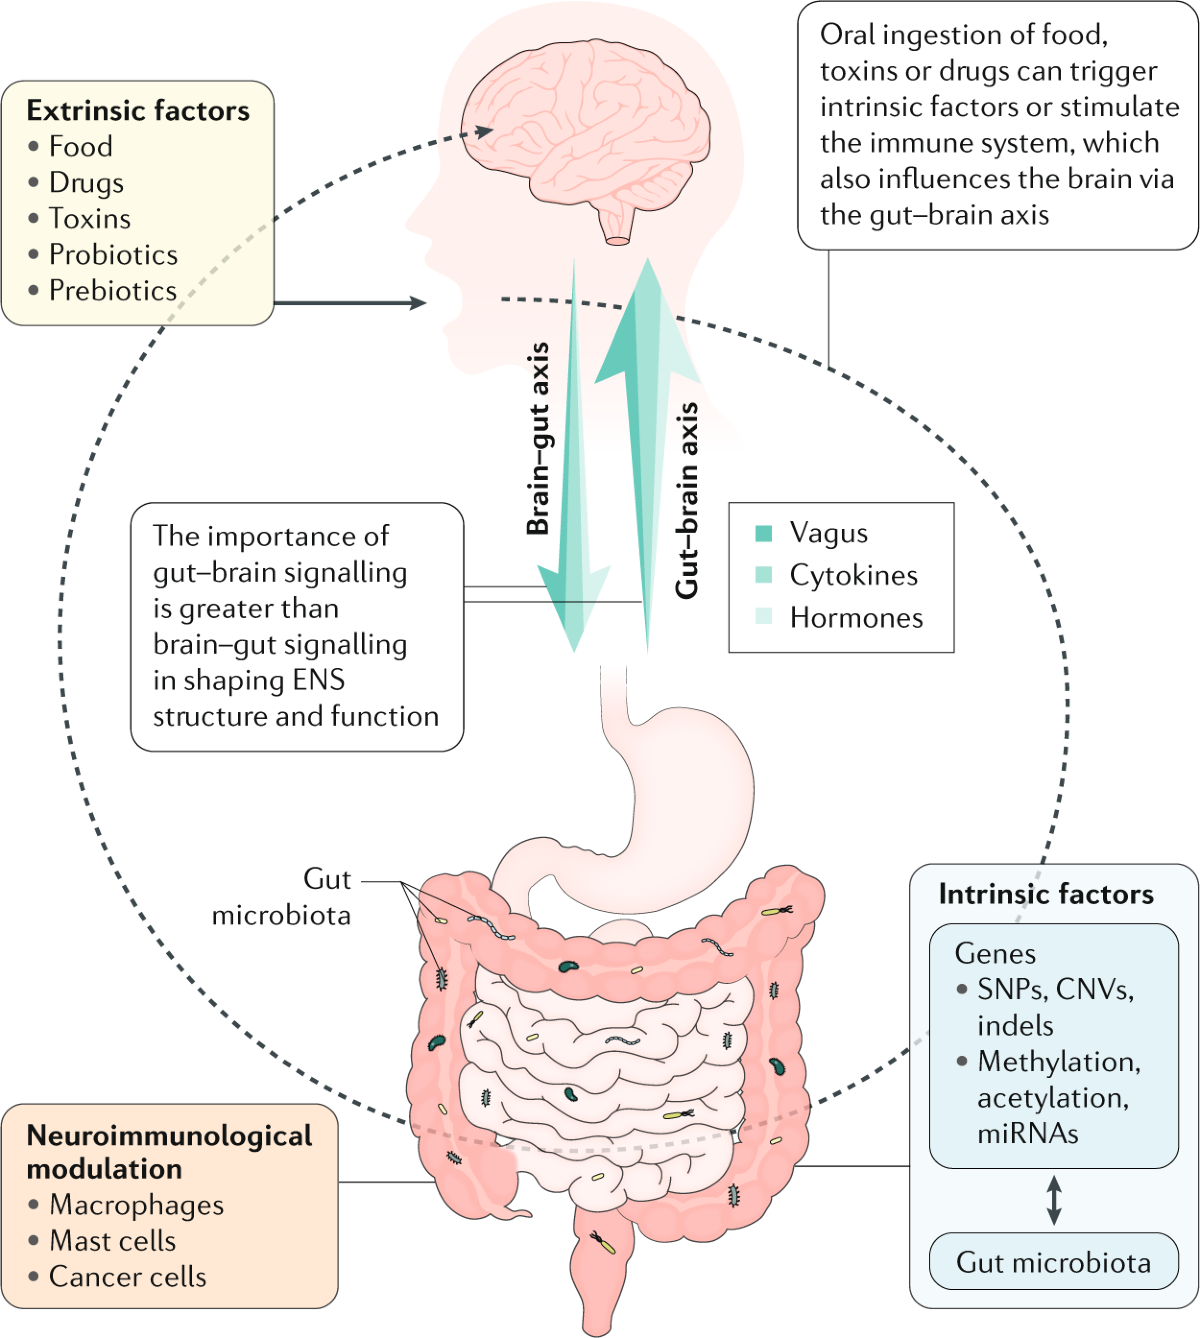

Enteric Nervous System

There is also an complete nervous system inside of the gut called the enteric nervous system. This controls the functions of the gut and communicates with the brain.